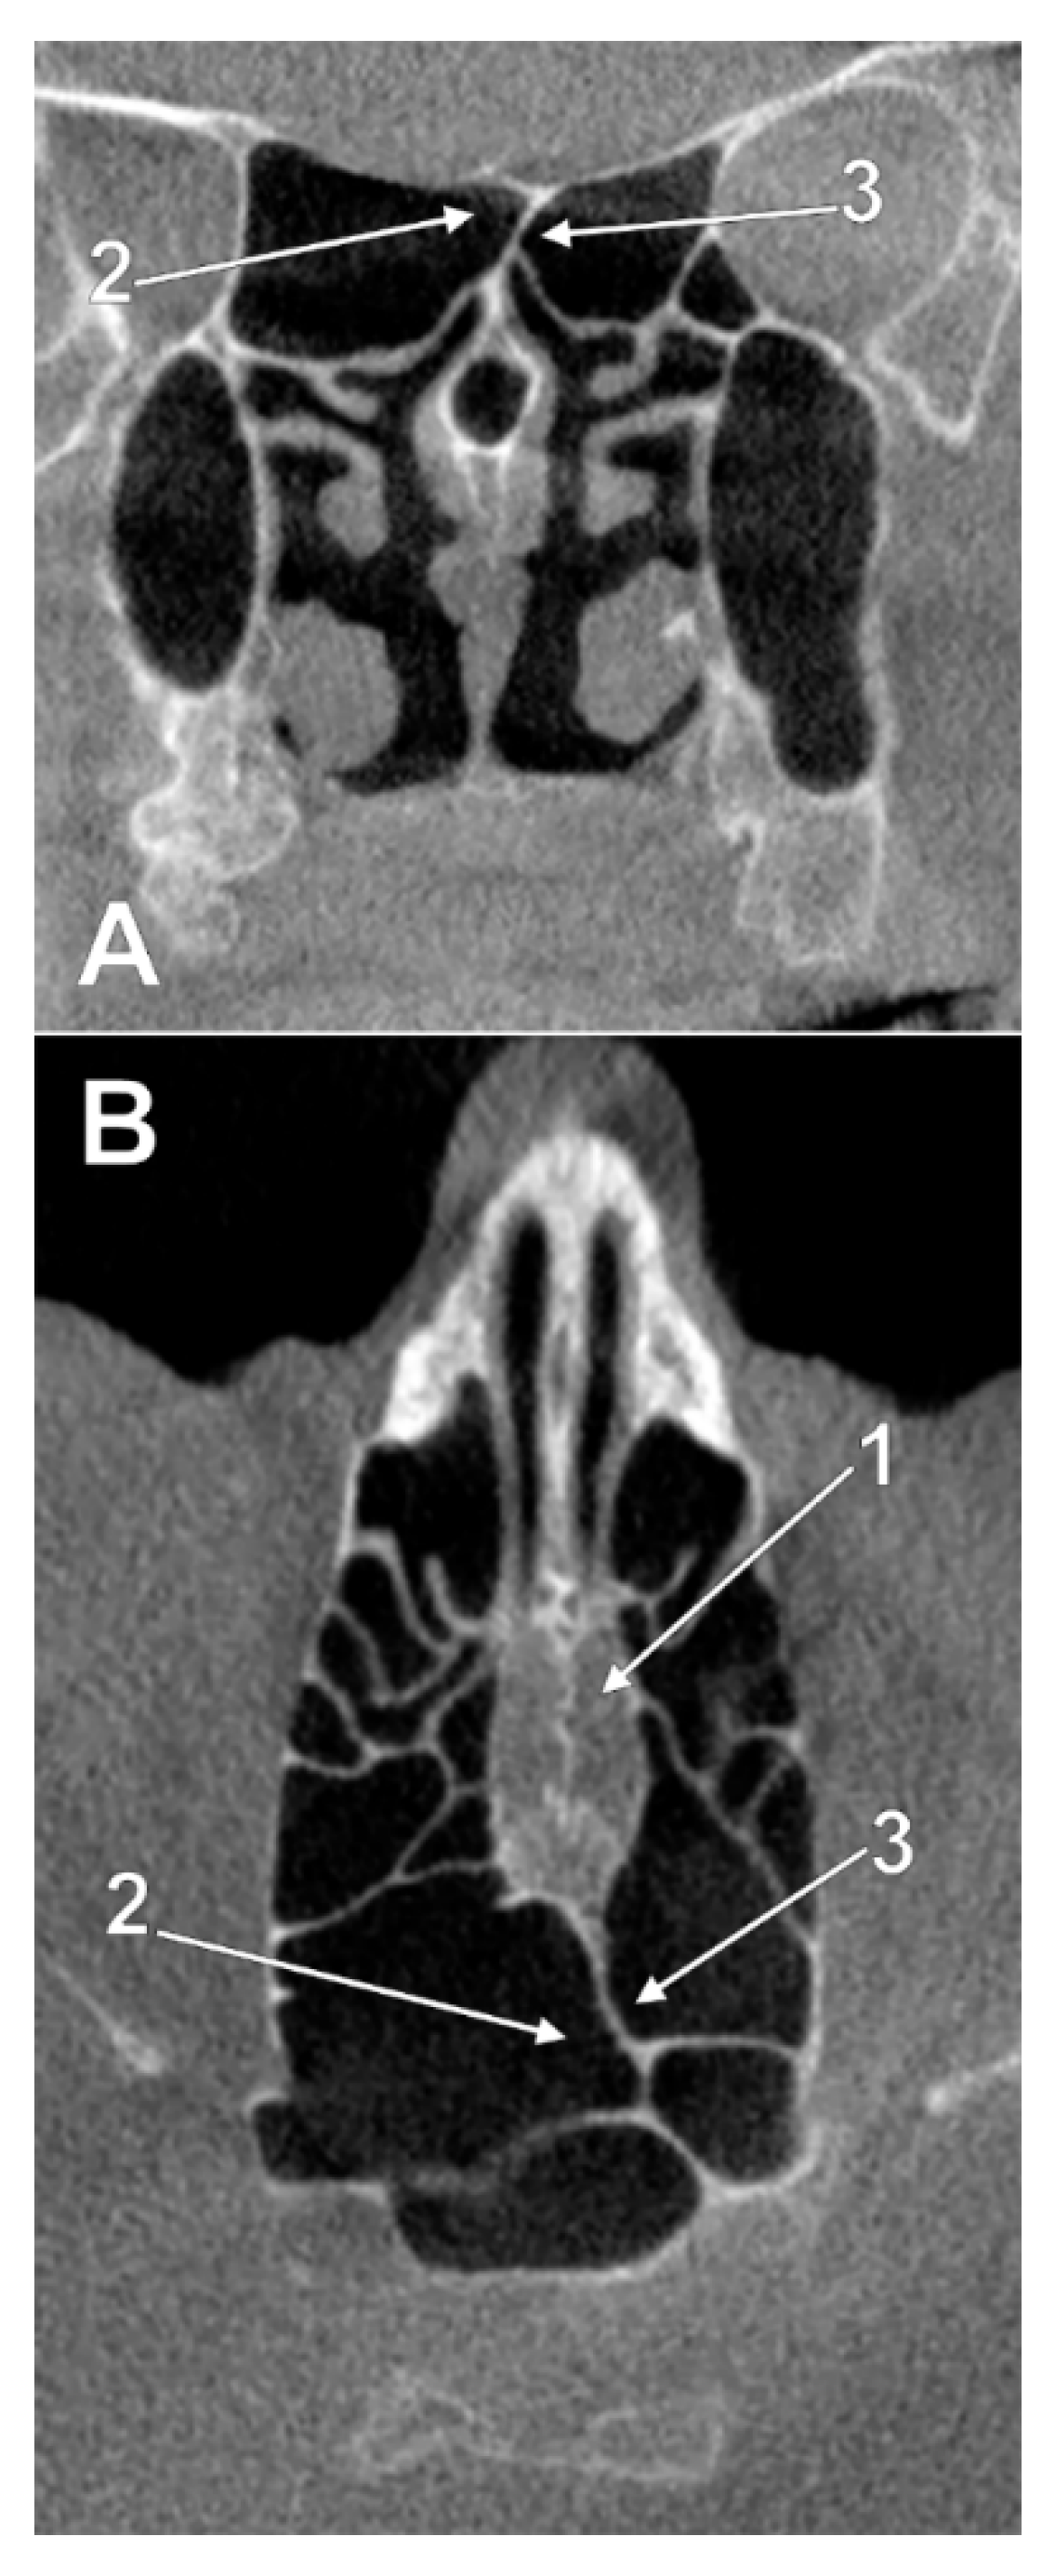

3.1. Ethmoidal Origin of Nasal Roof Pneumatizations

3.2. Sphenoidal Origin of Nasal Roof Pneumatization

3.3. Sphenoethmoidal (Onodi Cell) Origin of Nasal Roof Pneumatizations